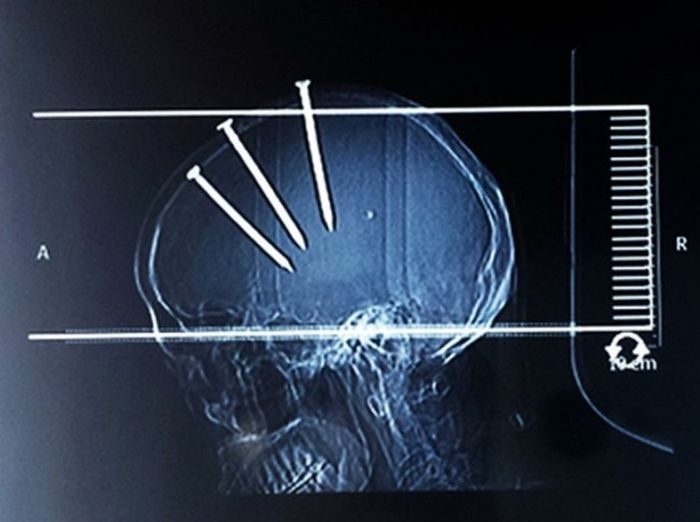

Я, конечно, не специалист, но по-моему, тут не нужен был рентген, чтобы понять, что произошло